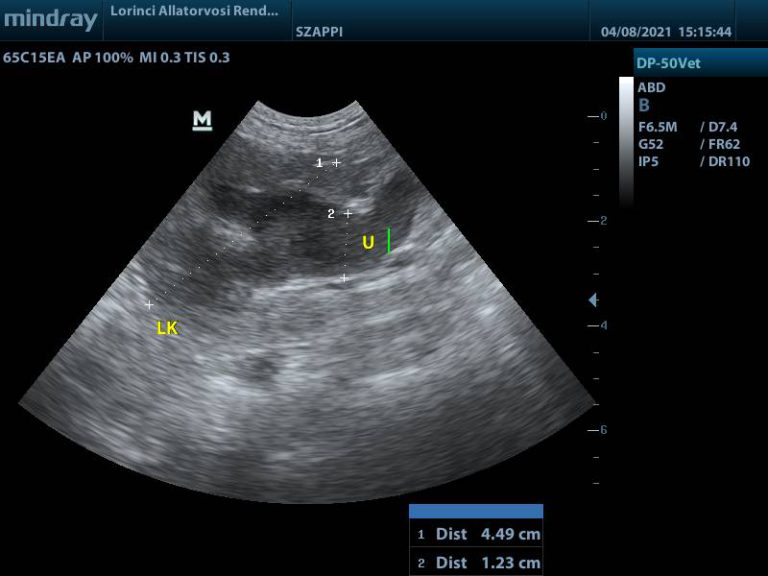

Hasi ultrahang

Húgyhólyag nagy részét kitöltő daganat

Megvastagodott hólyagfal és calcificatio

Bal vesemedence és urether tágulat

A hasi ultrahangvizsgálat során, telt hólyag mellett lehetőség van többek között a falszerkezet és falvastagság elbírálására. Az ép húgyhólyag fala kutyákban 3 mm-nél, macskákban 2 mm-nél nem vastagabb, sima felszínű, egyenletes. A falvastagságot kissé befolyásolja a hólyag teltsége, minél több vizelet van a hólyagban, annál jobban ellaposodik.

Ha a hólyag fala egyenetlen, megvastagodott, vagy massza türemkedik a hólyag üregébe – különösen a trigonum tájékán -, az aggodalomra adhat okot. Az ultrahang azonban önmagában nem különíti el a daganatos – és gyulladás miatti elváltozásokat, viszont a citológiával, illetve szövettani vizsgálattal együtt hasznos és fontos vizsgáló módszer.